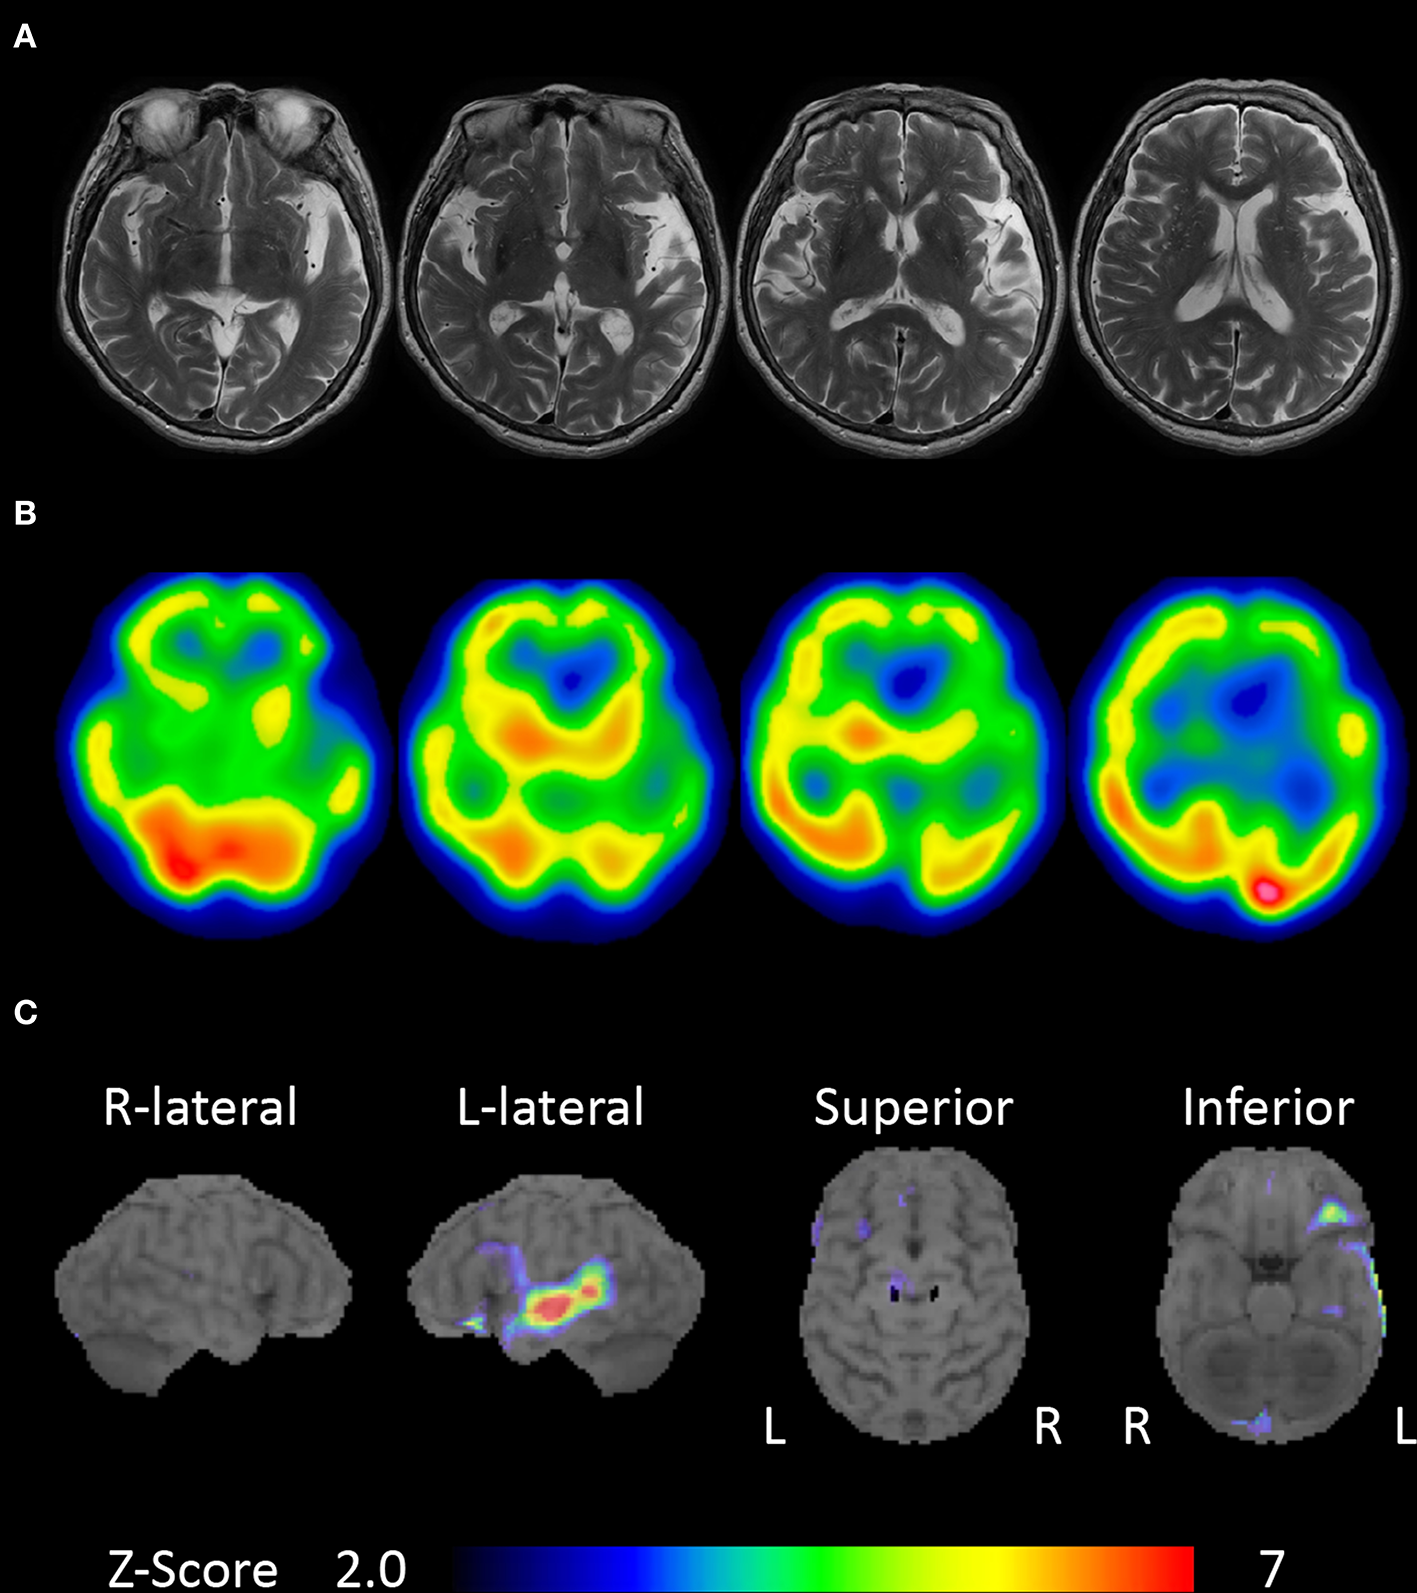

An 80-year-old, right-handed woman visited our hospital because of gradually progressive difficulty in speaking and recognizing spoken words. She had received 9 years of education. Speaking and recognizing spoken words had concurrently become challenging at around the age of 77 years. Except for the presence of cataract, her medical history was unremarkable. She was fully conscious and oriented at the initial visit. No abnormalities were detected on physical and neurological examinations, or routine laboratory tests. Brain magnetic resonance imaging revealed left-sided predominant atrophy of the bilateral perisylvian area (Figure 1A). There was no evidence of hemorrhage or ischemic lesion. N-Iso-propyl-p-[123I] iodoamphetamine single-photon emission computed tomography (SPECT) revealed predominant left-sided hypoperfusion of the bilateral frontal and temporal lobes (Figure 1B). To assess the patterns of hypoperfusion (5), SPECT data were analyzed with 3D stereotactic surface projections (SSP) (6). All SPECT scans underwent realignment, spatial normalization, and non-linear warping. The scans were sampled at 16,000 predefined cortical locations and projected on a 3D image. The voxel values of the patient's SPECT data were normalized to the whole brain's tracer uptake and compared with an age-matched normal database, yielding a 3D SSP Z score image. The abnormalities of cerebral hypoperfusion were displayed with a Z score map. Z scores were calculated using the following equation: Z score = (normal mean – patient mean) / (normal standard deviation). We used a Z score of 2 as the cutoff value in each voxel, and voxels with a Z score ≤ 2 were considered voxels without significantly decreased regional cerebral blood flow. Brain SPECT data analyzed with 3D SSP revealed relative hypoperfusion, mainly in the left superior temporal and inferior frontal gyri (Figure 1C).

Figure 1

Brain magnetic resonance imaging and single-photon emission computed tomography (SPECT). (A) Brain magnetic resonance imaging showing left-sided predominant atrophy of the perisylvian area. (B)N-Iso-propyl-p-[123I] iodoamphetamine SPECT showing left-sided predominant hypoperfusion of the bilateral frontal and temporal lobes. (C) Brain SPECT analyzed with 3D stereotactic surface projections (SSPs) showing relative hypoperfusion mainly in the left superior temporal and inferior frontal gyri.

Generalized auditory agnosia, as reported in cases of cerebrovascular disease (20) and neurodegenerative disease (7, 16, 21), is associated with bilateral temporal lobe lesions involving the primary auditory and auditory association cortices; our patient's lesions, identified using brain magnetic resonance imaging and SPECT, correspond to these previously elucidated areas. Moreover, brain SPECT analyzed with 3D SSP revealed relative hypoperfusion mainly in the left superior temporal gyrus, which is consistent with patterns of hypometabolism identified using positron emission tomography with 18F-labeled 2-fluoro-2- deoxyglucose (7). Therefore, in the context of past research, we suspect that generalized auditory agnosia in our case was induced by bilateral temporal lobe atrophy involving the superior temporal gyrus.